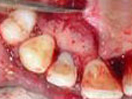

Regenerative Endodontic Procedure -

Regenerative Endodontic Procedure

Naseem Shah -

PRF Mediated REP in 21 with 18 Months Follow Up

Complete Bony Healing, Apex Closed, Lateral Wall Thickening- 15.5%